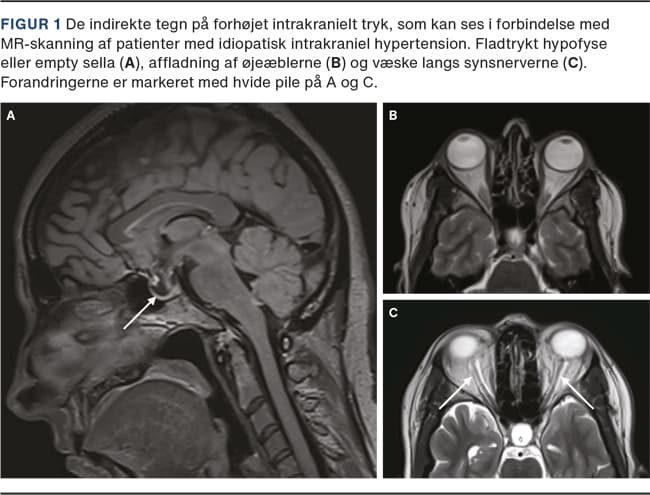

Såfremt der er bilaterale sinus transversus-stenoser eller unilateral stenose med modsidig hypoplasi samt en hæmodynamisk betydende trykgradient over stenosen, vil der være indikation for behandling [17]. Et kateter indføres UL- eller gennemlysningsvejledt via en punktur i halsvenen, og en guidewire føres retrogradt til sinus transversus. Under tilbagetrækningen af katereret udløses en selvekspanderende stent, som dækker stenosen (Figur 3). Der er sjældent behov for supplerende ballonangioplastik. Hjernens venesystem visualiseres simultant med indirekte cerebral angiografi med et kateter placeret i a. carotis interna via en lyske- eller håndledspunktur. Adskillige studier har vist, at stentning af stenoserne har effekt med ophævelse af den transstenotiske gradient og lindring af symptomerne [20].

Hos korrekt udvalgte patienter ses forbedring af papilødem og hovedpine hos hhv. 94% og 80%. 10% oplever dog behandlingskrævende recidiv af symptomerne [20], og 2% har komplikationer til behandlingen. Der er ikke rapporteret om dødelige komplikationer. Forbigående stenthovedpine er hyppig og ses hos ca. 30%. Stenthovedpinen beskrives typisk af patienten som nyopståede smerter i baghovedet, forskellig fra den hovedpine, som de kender fra deres grundsygdom, og karakteriseres som lokaliserede, unilaterale occipitale smerter, ipsilateralt til den side, hvor stenten er placeret. Smerterne varer typisk 2-4 uger, men der er ingen publicerede prognostiske studier om hovedpinens forløb. Stenttrombose er sjældent og ses hos < 1%, hvorfor det er vigtigt at supplere med pladehæmmende behandling [21].